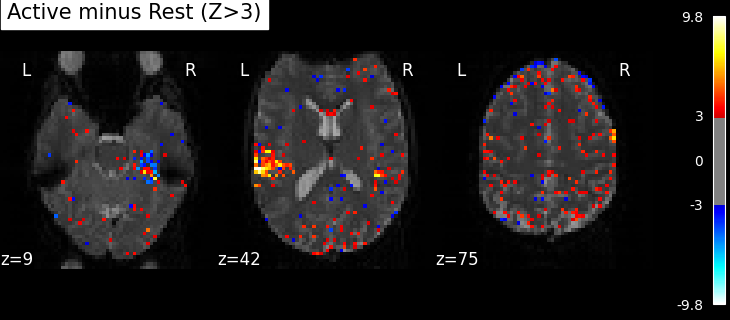

Plot thresholded z scores map¶

We display it on top of the average functional image of the series (could be the anatomical image of the subject). We use arbitrarily a threshold of 3.0 in z-scale. We’ll see later how to use corrected thresholds. We will show 3 axial views, with display_mode=’z’ and cut_coords=3.

plot_stat_map(

z_map,

bg_img=mean_img,

threshold=3.0,

display_mode="z",

cut_coords=3,

black_bg=True,

title="Active minus Rest (Z>3)",

)

plt.show()